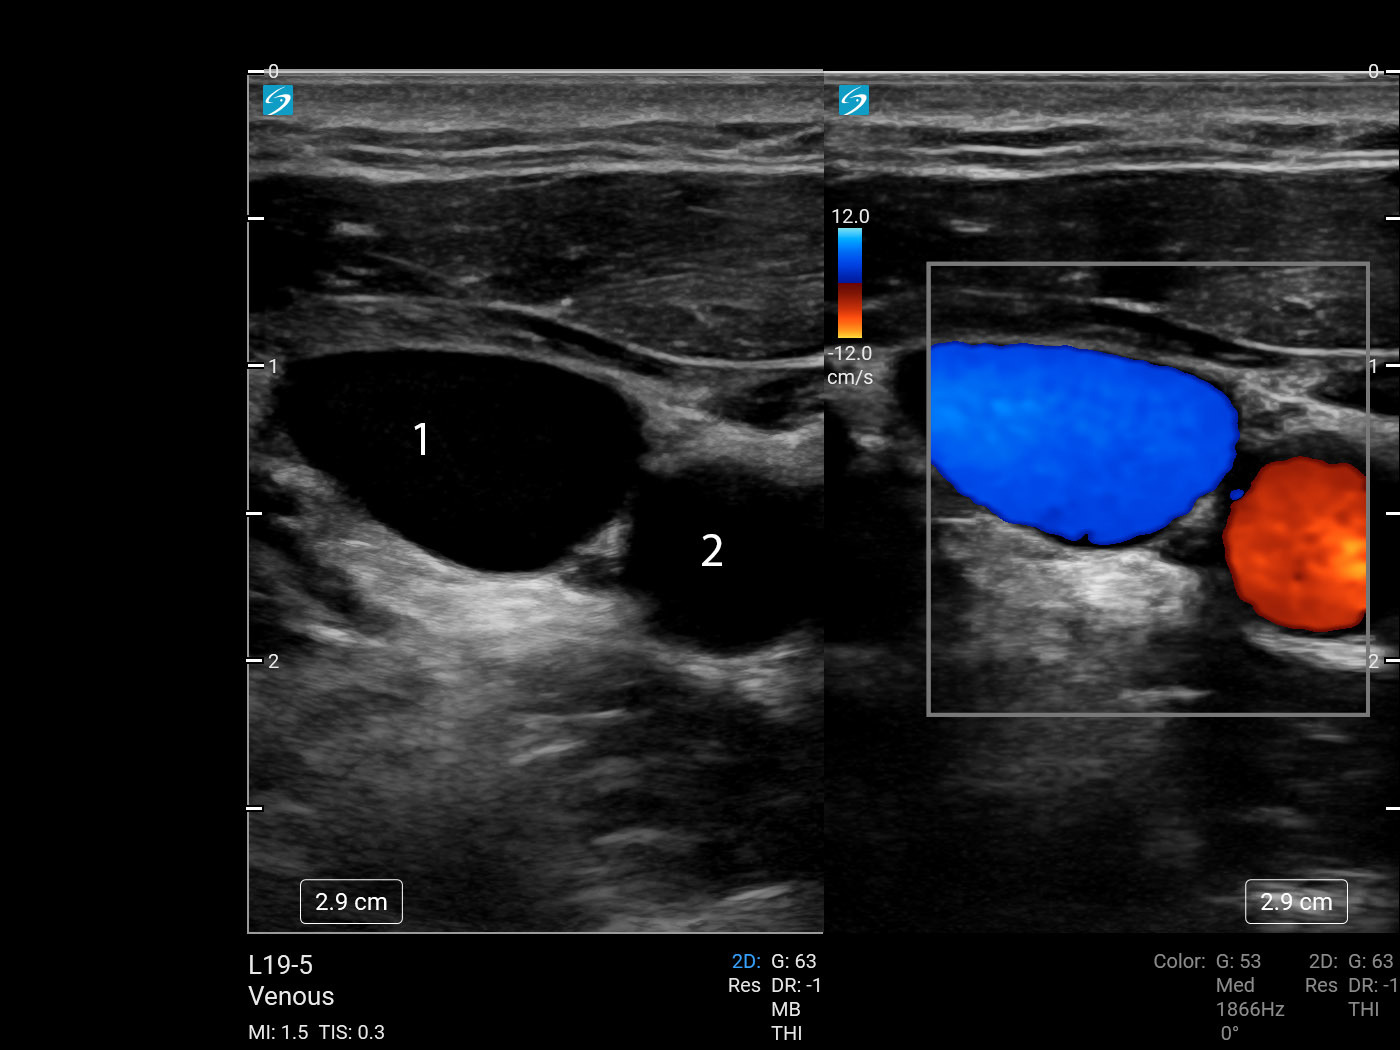

Vascular Internal Jugular Vein (IJV) (Sonosite PX L19-5) Image

1. Internal Jugular Vein (IJV)

2. Common Carotid Artery (CCA)